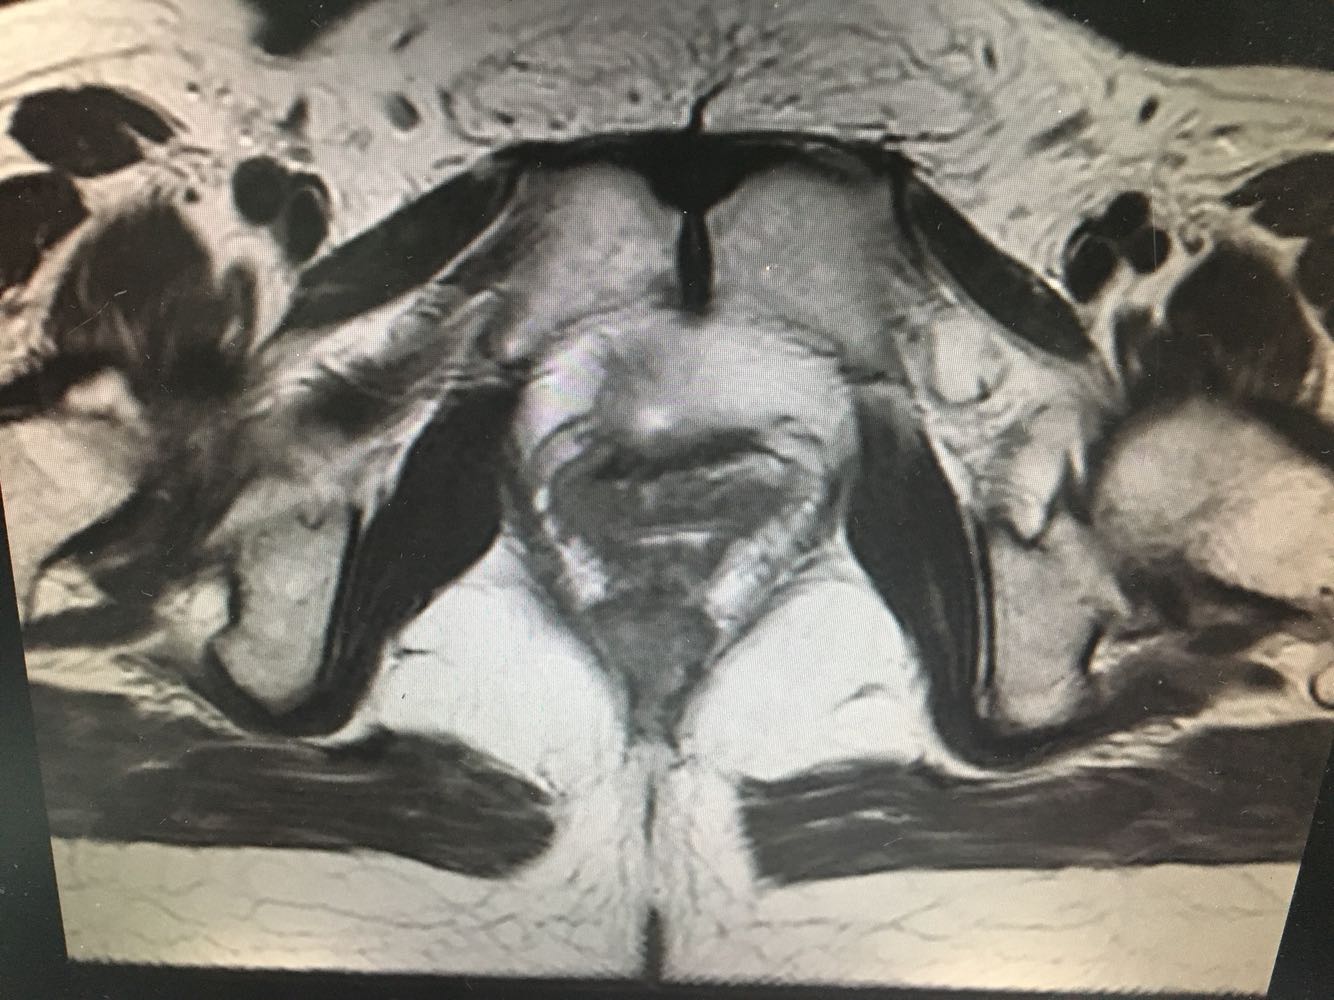

体检:神清,精神可,皮肤巩膜无黄染,轻度贫血貌,浅表巴结未及肿大,颈软,气管居中,双肺呼吸音清,未闻及干湿罗音,律齐,无杂音,腹平软,无压痛反跳痛,未触及明显肿块,肝肾叩击痛(-),移浊(-),NS(-)。        妇科检查:外阴:已婚已产式,阴道:畅,粘膜光,穹窿四周软,宫颈:增大约4cm,表面糜烂增生状,可见异型血管,触血(+)附件:未及明显异常,三合诊:双侧宫旁未及增厚。 5.辅助检查:【宫颈TCT】示不能排除高度鳞状细胞病变的非典型鳞状细胞癌(ASC-H)  【宫颈活检病理】示非角化型鳞状细胞癌,部分处浸润生长

诊断:宫颈恶性肿瘤(鳞癌,Ib1期) 诊疗方案:患者入院积极完善评估,行腹腔镜下广泛全子宫+双侧附件切除+双侧卵巢动静脉高位结扎+盆腔淋巴结清扫+腹主动脉淋巴结清扫+盆腔粘连分解术,术中见子宫增大如孕40+天,质中,表面光滑,活动尚好。现患者一般情况可。